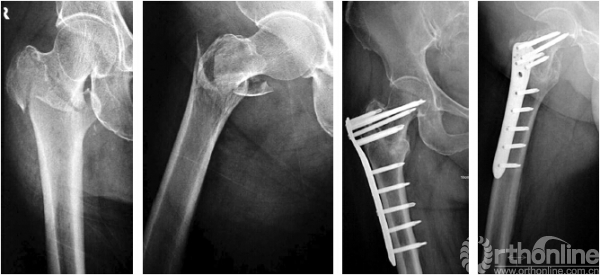

髓内固定组术后11例发生内固定相关并发症,并发症发生率为4.3%(11/257),包括髋螺钉退出2例、螺钉切出3例、螺钉穿入髋臼6例(图2)。其中8例骨折已愈合者取出内固定;3例骨折未愈合者分别于术后12、14、18个月改行股骨头置换。

图2 男,76岁,股骨转子间骨折伴外侧壁骨折 A 术前正侧位X线片示股骨转子间31A2.2型骨折伴外侧壁骨折 B 髓内钉治疗术后正侧位X线片示骨折复位,髓内钉位置良好 C 术后8周正侧位X线片示髓内钉穿入髋臼

目前,已有多篇使用倒置LISS接骨板治疗股骨转子部骨折的文献报道,并取得了较好的效果。Zhou 等前瞻性比较了LISS 与PFNA 治疗股骨近端骨折的疗效,LISS组共28例,PFNA组共36例,两组患者术中出血量及术后并发症及髋关节功能均无显著差异;李忠等比较了LISS与PFN治疗转子下骨折的优劣,两组患者在愈合率、术后膝关节功能方面无显著差异;陈松等使用DHS、PFN及股骨近端锁定接骨板治疗112例老年转子间骨折患者,在手术时间、术中出血量、愈合时间及术后髋关节功能方面,PFN 及股骨近端锁定接骨板组均优于DHS组,但PFN及股骨近端锁定接骨板组间无显著差异;Yao等前瞻性比较LISS与PFN治疗老年转子间骨折患者的效果,两组患者手术时间、术中出血量及术后髋关节功能无显著差异。以上文献的比较结果发现,在术后关节功能、并发症方面,锁定接骨板固定较髓内固定并无明显差别,这提示对于外侧壁骨折、梨状窝粉碎性骨折移位、转子部冠状面劈裂等髓内固定困难的病例可用LISS接骨板作为内固定物。本研究倒置LISS固定组及髓内固定组术后骨折愈合时间及髋关节功能均无差异,但倒置LISS固定组的内固定相关并发症发生率较髓内钉固定组高。这可能与LISS的偏心固定结构、近端螺钉与钢板近乎垂直而导致螺钉尾端与钢板接触处剪切应力过大、骨折复杂程度相对较高有关(均在31A2.2型以上)。另外,本组病例也显示了在外侧壁存在骨折时,倒置LISS接骨板可能比髓内固定更具有优势(图3)。

图3 男,69岁,股骨转子间骨折伴外侧壁骨折A,B 术前正、侧位X线片示股骨转子间31A2.2型骨折伴外侧壁骨折C,D 采用倒置LISS接骨板固定,3个月后正、侧位X线片示骨折愈合